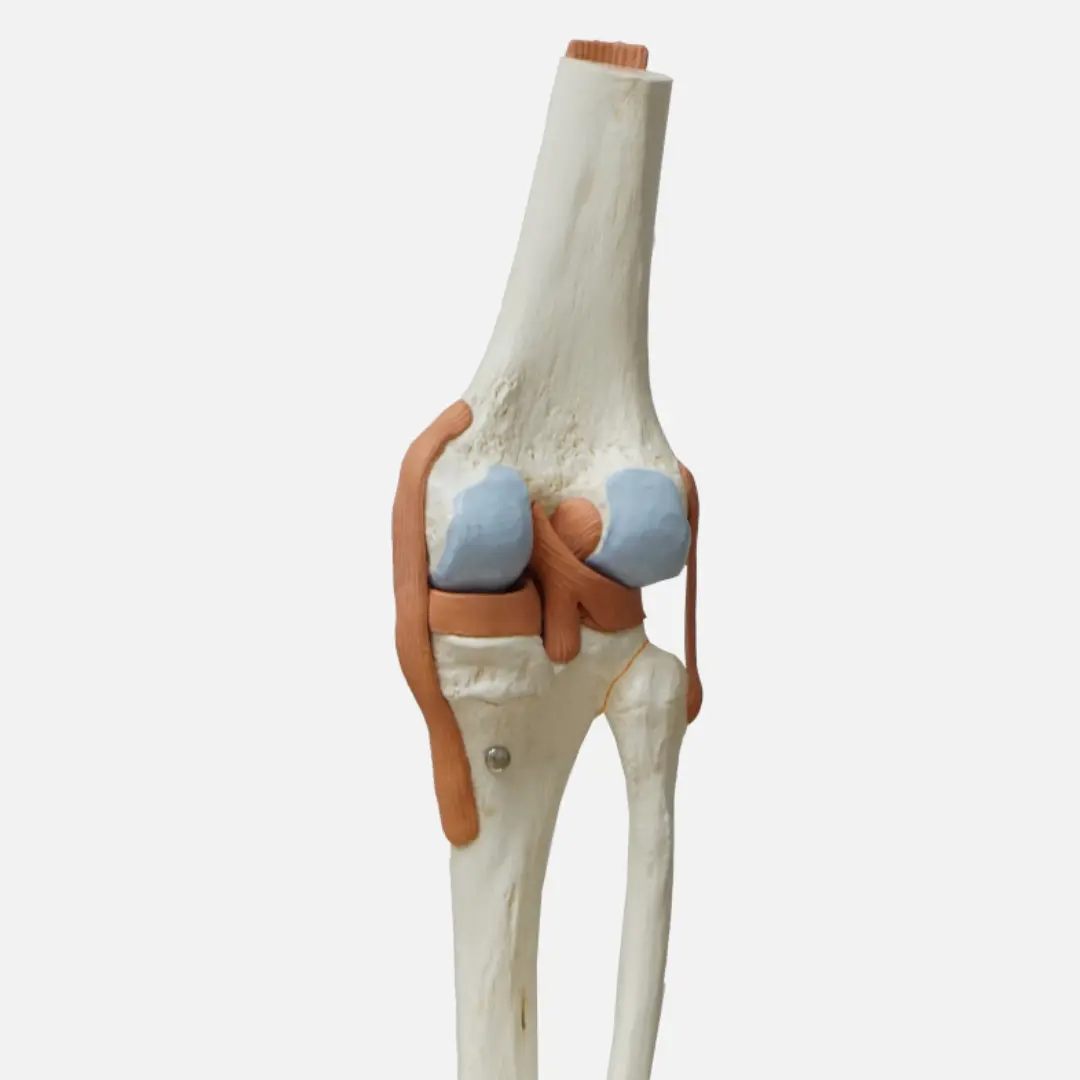

퇴행성 관절염은 가장 흔한 관절염으로, 주로 관절 연골의 손상으로 인해 발생해요. 초기증상은 연골이 닳기 시작하면서 나타난답니다.

- 자가면역 반응: 면역 체계가 관절을 감싸는 활막(synovial membrane)을 공격하여 염증을 유발하는 것이 근본적인 원인이에요. 활막은 관절액을 생성하여 관절을 윤활하는 역할을 하는데, 여기에 염증이 생기면 관절이 붓고 통증을 유발한답니다.